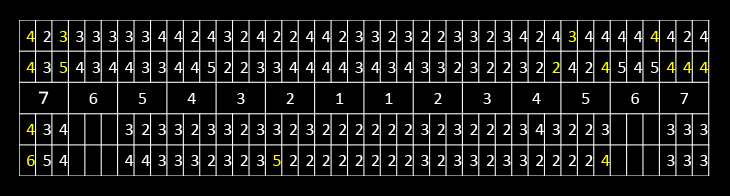

初診時デンタル及びプロービングチャート

右上6番7番右下7、左下7番および左上7番には深いポケットがみられます。

左下7の近心には垂直性の骨欠損を認めます。

X線上では分かりにくいですが右下7には歯根に及ぶカリエスを認め、

また右下5には破折したリーマーと根尖病変を認めました。

右下5番は残念ながら再治療が不可能と判断し抜歯、右下7番もむし歯が進行しすぎているため保存ができないと判断し抜歯としました。

患者さんはなくなってしまった部位にたいして、インプラント治療を希望されたためインプラントにて治療をすることにしました。

CT所見

ほぼ骨内には埋入できましたが、骨の厚みが足りないため、人工骨を移植し縫合しました。

埋入後6カ月口腔内写真及びデンタル

インプラントの周囲に固い歯茎(角化歯肉)があるとしっかりと歯ブラシがあてることができます。

インプラントの周囲に固い歯茎を作るために歯茎(角化歯肉)の移植を行いました。